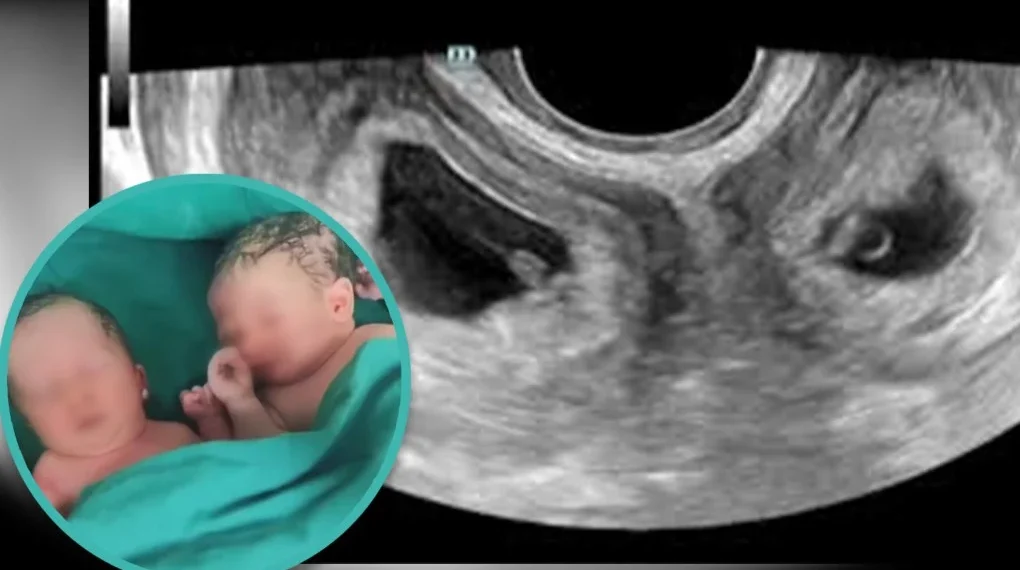

ഷാങ്സി: ഇരട്ടക്കുട്ടികൾക്ക് ജന്മം നൽകിയ ഒരു ചൈനീസ് യുവതി വാർത്താ തലക്കെട്ടുകളിൽ നിറയുകയാണ്. ഇരട്ടകൾക്ക് ജന്മം നൽകുന്നതിൽ അസ്വാഭാവികതയില്ലെങ്കിലും ഈ യുവതിയുടെ പ്രസവം മെഡിക്കൽ ലോകത്തെ തന്നെ അമ്പരപ്പിച്ചിരിക്കുകയാണ്. രണ്ട് ഗർഭപാത്രങ്ങളിൽ നിന്നാണ് യുവതി ഇരട്ടക്കുട്ടികൾക്ക് ജന്മം നൽകിയത് എന്നതാണ് അമ്പരപ്പിന് കാരണം. ചൈനയുടെ വടക്കുപടിഞ്ഞാറൻ മേഖല സ്വദേശമായ ലി ആണ് രണ്ട് ഗർഭപാത്രങ്ങളിലൂടെ ഓരോ കുട്ടികൾക്ക് ജന്മം നൽകിയത്.

ചൈനയിലെ ഷാങ്സി പ്രവിശ്യയിലെ ആശുപത്രിയിൽ ഈ മാസമാണ് ലിയുടെ പ്രസവം നടന്നത്. ‘യൂട്രസ് ഡൈഡൽഫിസ്’ എന്ന അത്യപൂർവ അവസ്ഥ ആണ് യുവതിക്കെന്ന് കണ്ടെത്തിയിരുന്നു. അണ്ഡാശയവും അണ്ഡനാളവും ഉൾപ്പെടെയുള്ള, പൂർണ വളർച്ച പ്രാപിച്ച രണ്ട് ഗർഭപാത്രം രൂപപ്പെടുന്ന അവസ്ഥയാണ് യൂട്രസ് ഡൈഡൽഫിസ്. ലോകത്ത് സ്ത്രീകൾക്കിടയിൽ 0.3 ശതമാനം പേർക്ക് മാത്രം സംഭവിക്കുന്ന അവസ്ഥ…

ഇരട്ടകളായ ഒരു ആൺകുട്ടിക്കും പെൺകുട്ടിക്കും ആണ് ഇരു ഗർഭപാത്രങ്ങളിലൂടെ ലൂടെ യുവതി ജന്മം നൽകിയത്. യുവതിയുടെ ഗർഭം എട്ടര മാസമായപ്പോഴാണ് ഇരട്ടകൾക്ക് ജന്മം നൽകിയത്. ദശലക്ഷത്തിൽ ഒരാൾക്ക് മാത്രം സംഭവിക്കുന്ന അത്യപൂർവ കേസാണിതെന്നാണ് ഡോക്ടർമാർ വ്യക്തമാക്കുന്നത്. സ്വാഭാവിക ഗർഭധാരണത്തിലൂടെ രണ്ട് ഗർഭപാത്രങ്ങളിൽ ഓരോന്നിലും ഗർഭിണിയാകുന്നത് വളരെ അപൂർവമാണ്. ചൈനയിൽ നിന്നും വിദേശത്തുനിന്നും അത്തരം രണ്ട് കേസുകളെ കുറിച്ച് മാത്രമേ കേട്ടിട്ടുള്ളൂവെന്നും അവർ കൂട്ടിച്ചേർത്തു…